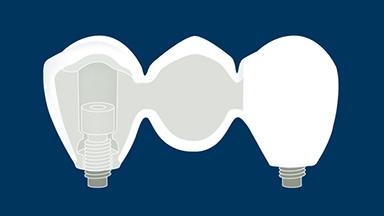

As próteses fixas implantossuportadas visam fornecer substitutos para dentes ausentes que são capazes de resistir à demandas funcionais e imitar com acurácia a estética das unidades denteais ausentes. Idealmente, a prótese deve ser indistinguível da dentição ao redor. Para atingir este objetivo, o clínico deve selecionar os melhores materiais disponíveis para enfrentar os desafios da situação clínica. Este módulo discutirá os materiais dentários disponíveis para a fabricação de próteses implantossuportadas e os princípios básicos envolvidos na seleção do material mais adequado para cada caso.

- descrever as propriedades ideais para materiais dentários usados na fabricação de próteses fixas implantossuportadas (PFs)

- listar os materiais disponíveis para fabricar PFs implantossuportadas

- classificar os materiais disponíveis de acordo com as propriedades ideais para materiais de PFs implantossuportadas